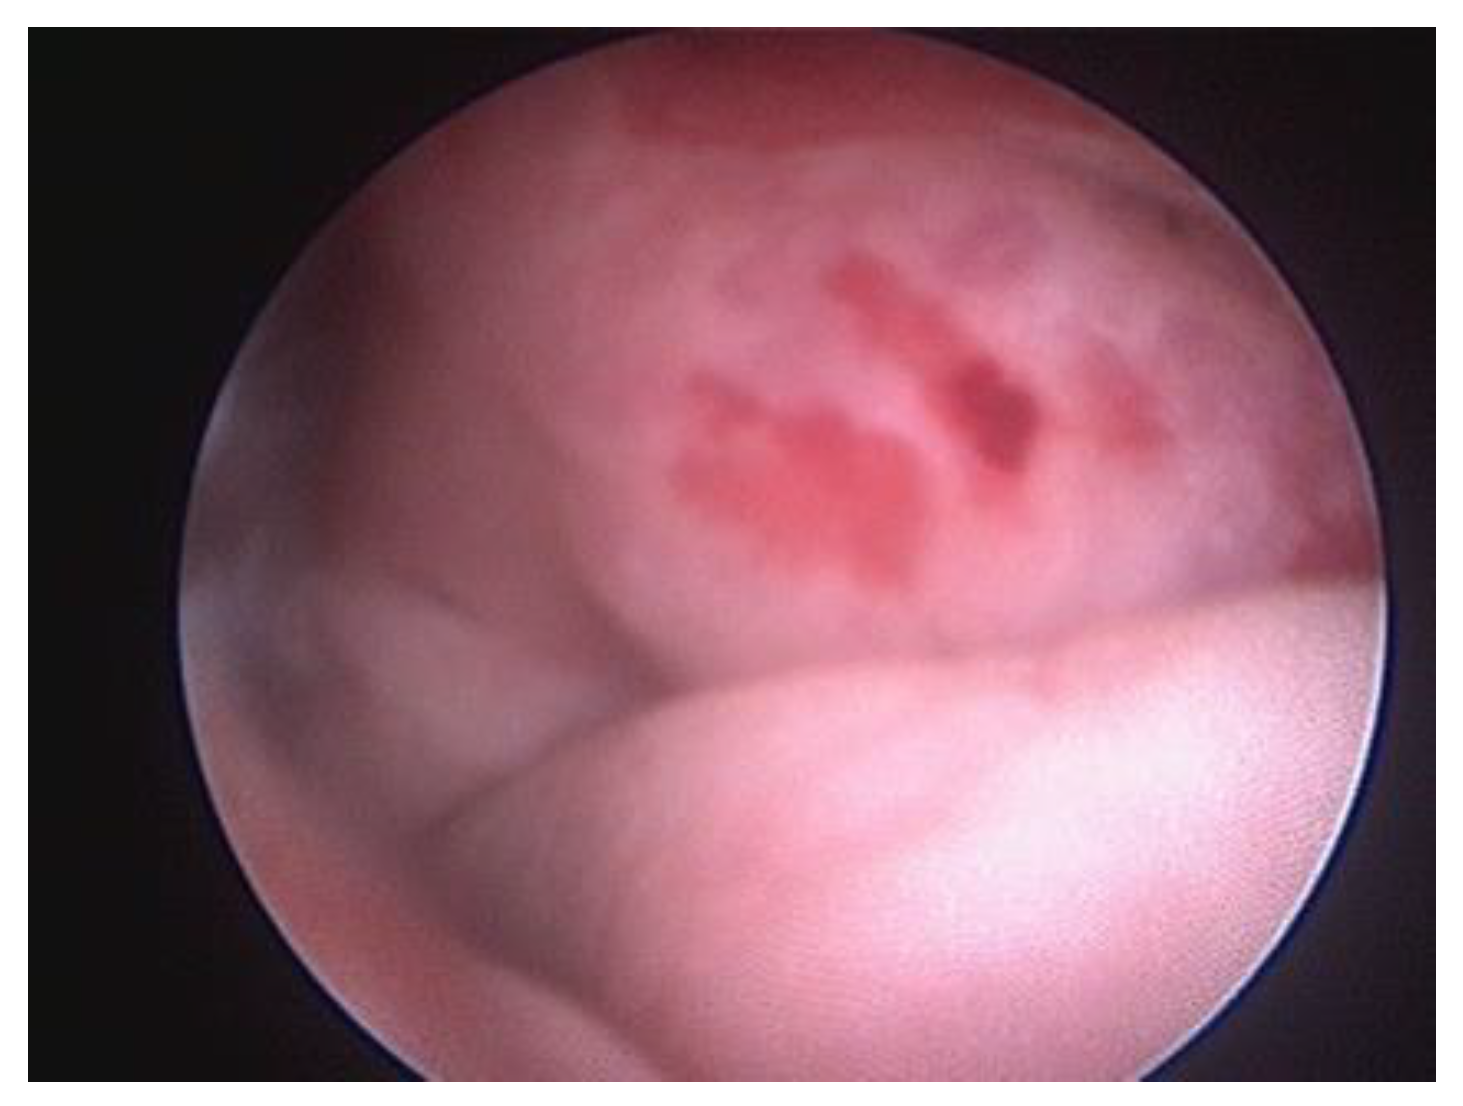

The vestibule is examined for foreign bodies, mucosal lesions, hyperemia, blood, and anatomical abnormalities [12]. Besides occasional foreign bodies and mucous follicles, abnormalities in the vestibule are rarely found; also, vaginal leakage may be seen in young dogs with urinary incontinence of ectopic ureters [2]. Urinary incontinence is an increasing problem in young female dogs, sometimes caused by a congenital abnormality called ureteral ectopy. This condition occurs when one or both ureteral openings are located further down from the bladder’s trigone. In the case of ectopic ureters, a basin shape of the ureter and its extension can be observed. Urethral sphincter mechanism incompetence is the primary reported cause of urinary incontinence in adult bitches. Ectopic ureters in dogs are a congenital condition in which the ureters, the thin tubes meant for connecting the kidneys to the bladder, bypass the bladder and instead connect directly to the urethra or vagina. Endoscopy is considered a sensitive method for detecting these abnormal or atypical openings (Figure 6). A cystoscopy is a valuable procedure for evaluating the image inside the bladder. It is beneficial to examine the vesical trigone, the ureteric orifices and the internal urethral orifice [10].

Figure 6. Ectopic ureter in a 4-month female dog terminating in the proximal urethra.